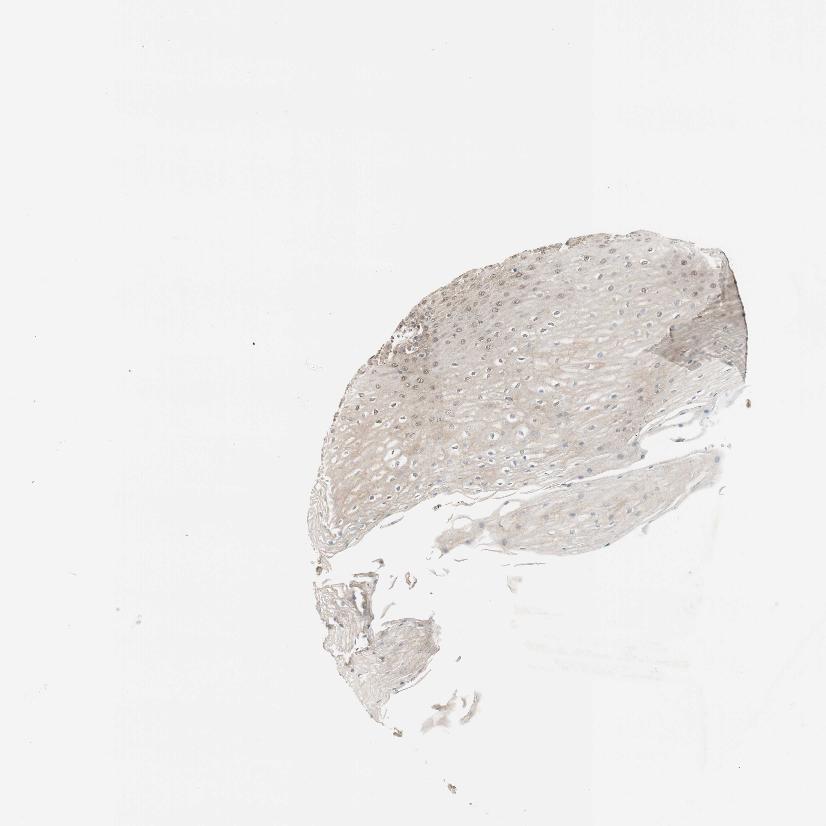

ESOPHAGUS - Antibody stainingi

Antibody staining in the annotated cell types in the current human tissue is reported as not detected, low, medium, or high, based on conventional immunohistochemistry profiling in selected tissues. This score is based on the combination of the staining intensity and fraction of stained cells.

Each image is clickable and will lead to virtual microscopy that enables deeper exploration of all samples and also displays staining intensity scores, fraction scores and subcellular localization as well as patient and tissue information for each sample.

Antibody HPA008399Antibody HPA017017Antibody CAB015221

Squamous epithelial cells MediumHighHigh